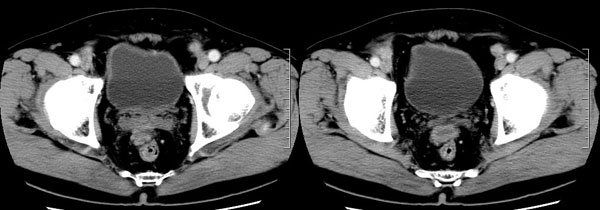

| 男性,69岁。自2个月前开始无意中发现左侧阴囊内一鸡蛋大小肿物,当时无伴疼痛等不适,未予重视。肿物逐渐增大,近段时间常伴左会阴部、腹股沟区牵扯不适,并于2周前在我院门诊行彩超检查提示“左侧附睾肿瘤可能,左侧睾丸鞘膜积液”。 专科检查:左侧阴囊肿大,其内可触及一鹅蛋大小肿物,表面光滑。肿物前部呈囊性感,后部质硬,按压无疼痛,无缩小,活动度良好。左侧睾丸未触及,透光试验(±)。                 王仕学发言:左侧睾丸见一密度不均肿块,边缘清楚,周围见水样密度影;考虑睾丸生殖细胞性肿瘤可能性大. 睾丸肿瘤占生殖系统肿瘤的3%-5%,占男性恶性肿瘤的0.5%-1.0%,其中生殖细胞性肿瘤占95%.睾丸肿瘤包括生殖细胞和非生殖细胞肿瘤两大类,前者占95%以上,后者不到5%.非生殖细胞肿瘤虽少见,但种类繁杂,主要有支持细胞、间质细胞和支持细胞-间质细胞瘤等功能性肿瘤,和间皮瘤、腺癌、横纹肌肉瘤、粘液性囊腺瘤、纤维上皮瘤、黑素神经外胚瘤、淋巴瘤等附属组织肿瘤。不同的病理类型的睾丸肿瘤发病率高峰不同,睾丸癌多发于35岁以前,精原细胞瘤发病高峰为30-35岁。精原细胞瘤约占睾丸肿瘤的60%,发病高峰在30-35岁。85%的患者睾丸有明显肿大,肿瘤局部侵犯力较低,肿瘤一般有明显界限。 手术:行“左侧附睾、睾丸、精索切除术”。 病理诊断:(左睾丸、附睾)肿物,为低分化腺癌。另送检(左精索远端)肿物,镜下亦为低分化腺癌。 免疫组化:ck(l)(++++)、cea(+++)、ca19-9(-)、psa(-)、plap(-)、p53(-)、vimentin(-)。 原贴地址:http://www.radinet.com.cn/forum_view.asp?forum_id=4&view_id=30707 |